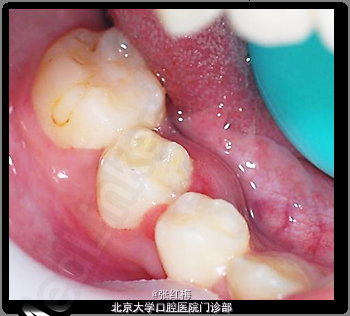

9岁儿童,女 主诉:右下后牙肿痛2天,伴舌侧牙龈肿痛,求治。 现病史:患儿3周前右下后牙畸形中央尖折断,行畸形中央尖备洞充填治疗,2周后出现右下后牙自发痛夜间痛,时间短暂,未就诊,3周后右下后牙肿痛,舌侧牙龈肿痛就诊求治。

45牙合面充填体完好,边缘密合,叩痛(+),松I0,冷热测均无反应,舌侧牙根对应粘膜见1×1.2cm2 脓包扪诊有波动感,X线:发育8-9期,根中下1/3分成两根,根尖孔喇叭状,根尖周低密度影。